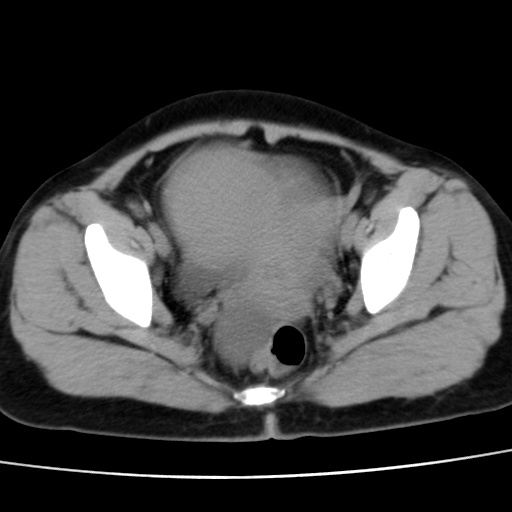

子宫多发肌瘤吗

多发性子宫肌瘤.

考虑多发子宫肌瘤,子宫直肠窝双囊性占位,另直肠周围脂肪密度增高,不知有何病史

支持考虑多发子宫肌瘤~!子宫直肠陷凹积液?

支持考虑多发子宫肌瘤~!子宫直肠陷凹积液!

子宫肌瘤,宫体部后方见液性密度影,是肠道还是子宫与直肠陷窝积液不好说,我觉得它的位置有点高

支持考虑多发子宫肌瘤!子宫直肠陷凹积液!

患者发热,而子宫直肠窝液性灶有明显边缘且局限且囊性,不除外为包裹性积液或脓肿

支持考虑多发子宫肌瘤,子宫直肠陷凹积液可能。

考虑多发子宫肌瘤

1)考虑子宫肌瘤可能性大。2)子宫后方囊性占位性病变,不排除卵巢囊肿可能。

考虑多发子宫肌瘤。子宫后方囊性占位性病变,不排除卵巢囊肿可能。